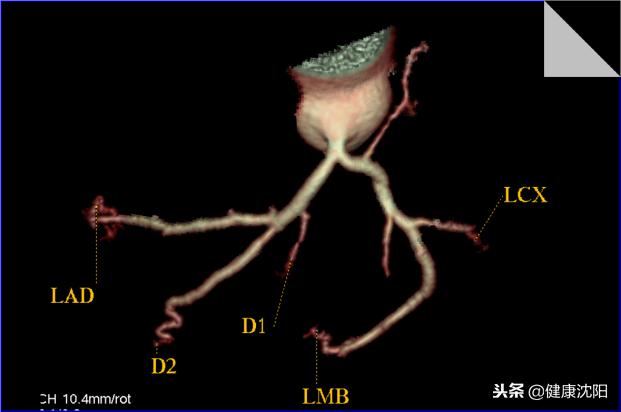

VR三维显示可以直观显示血管的大体形态、解剖,可以对病变进行明确的定位、定性诊断,可以直观地显示血管狭窄、血管瘤、动静脉畸形等病变,还可以间接判断血管壁的病变,进而提供进一步检查的必要性。CTA检查的VR技术实现了无创检查就能了解自己血管形态的目的。

显示左冠脉血管的解剖形态及分布